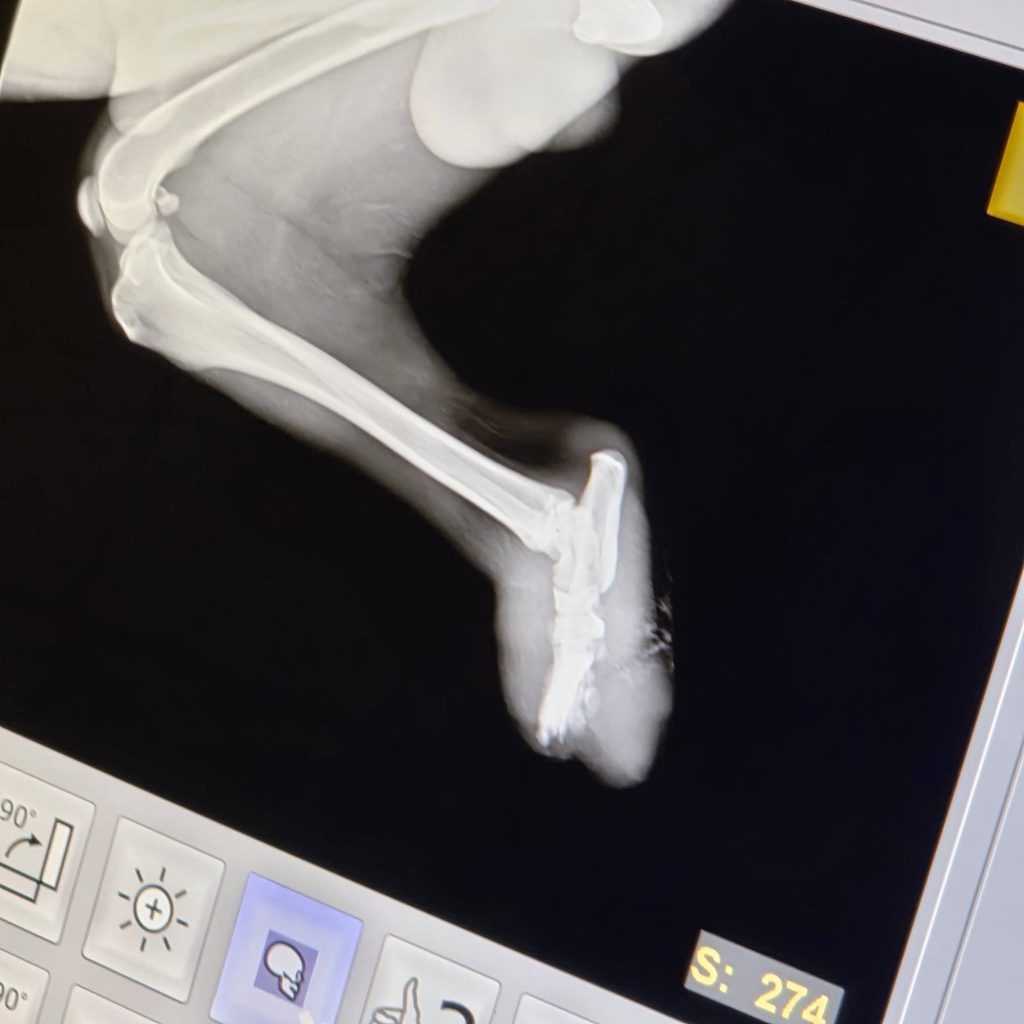

Sicher ist: Kein Zug hat ihm die Beine abgetrennt.

Die Verletzungen an beiden Hinterbeinen sind nicht zur gleichen Zeit entstanden. Es ist leider sehr wahrscheinlich, dass sie absichtlich verursacht wurden – unser Verdacht geht in Richtung einer Drahtschlinge.

Vor einigen ist unsere ungarische Tierschutzkollegin Betty schließlich zu ihm gefahren und hat ihn ins Krankenhaus gebracht, wo er sofort behandelt wurde. Einer der Stümpfe ist sogar auf dem Parkplatz der Klinik abgefallen, als er aus dem Auto gehoben wurde.